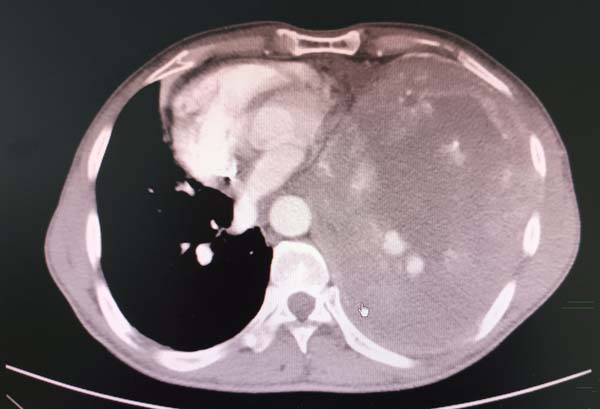

家住山西的魏大叔今年56岁,是三十几年的煤矿工人,被尘肺病困扰多年。今年春节,魏大叔出现胸闷并逐渐加重,在当地医院检查胸部CT显示,一个“大瘤子”占满胸腔的三分之二体积。这对一个家庭来说无疑是个致命的打击,原来的大汉,现在躺着睡觉都困难了;眼见魏大叔症状加重,儿子带着父亲来北京就诊,在多家医院求医,给出一致的答案:手术难度太大,生还机会较小……

患者来院后门诊CT显示,瘤体巨大几乎占满整个胸腔,血管受压很难辨认,石主任首先组织科内医师进行病例讨论,大家一致认为:患者自2月份就诊以来,肿瘤生长迅速,药物治疗无效,手术是患者唯一的希望,但手术风险很大。石主任立即组织MDT会诊,多次与呼吸内镜团队、介入科、麻醉科、重症监护室、普外科沟通病情,针对手术前的准备及术中可能出现的情况、术后处理措施,多次交流诊疗意见。